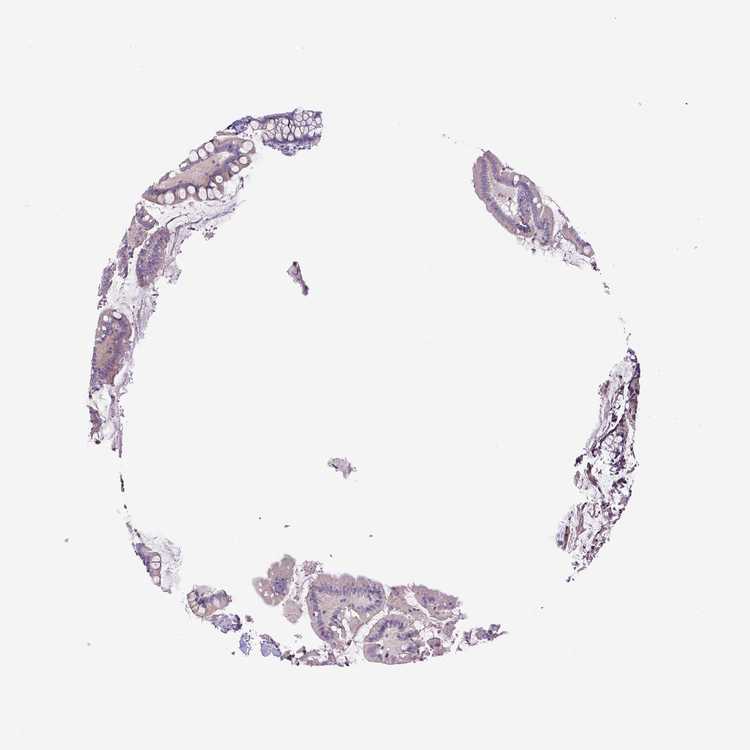

SMALL INTESTINE - Antibody stainingi

Antibody staining in the annotated cell types in the current human tissue is reported as not detected, low, medium, or high, based on conventional immunohistochemistry profiling in selected tissues. This score is based on the combination of the staining intensity and fraction of stained cells.

Each image is clickable and will lead to virtual microscopy that enables deeper exploration of all samples and also displays staining intensity scores, fraction scores and subcellular localization as well as patient and tissue information for each sample.

Antibody HPA031567Antibody HPA031568Antibody CAB002495Antibody CAB072868

Glandular cells Not detectedMediumNot detectedNot detected